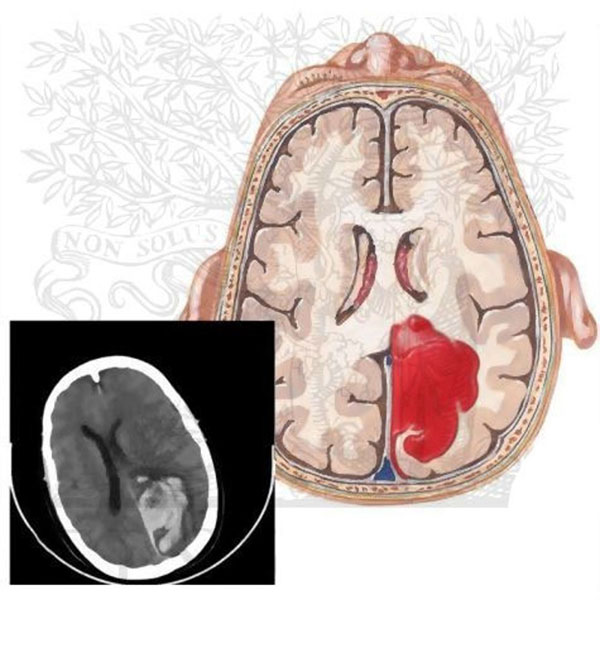

به سلول های خونی که در بخشی از مغز شکل آن ها ژله ای یا نیمه جامد شده است لخته خون در مغز می گویند. روند لخته شدن خون در مواردی نظیر پارگی رگ و یا بریدگی در سطح بدن برای زنده ماندن امری طبیعی و لازم می باشد. اما این لخته شدن خون اگه در رگ ها و مویرگ های مغز و بدن تشکیل شود باعث بروز حوادثی خطرناک می گردد. این لخته خون ها خود به خود از بین نمی روند و باید در صورت تشخیص آن ها فرد بیمار تحت درمان قرار گیرد.

لخته خون در مغز به واسطه ی انبوهی از سلول های خون که به حالت ژله ای تبدیل می شوند و باعث گرفتگی و انسداد رگ های مغزی می گردد به وجود می آید. هنگامی که بر اثر حادثه ای خون به حالت لخته در می آید، به صورت طبیعی از بین نمی رود و درمان آن باید تحت نظر پزشک مربوطه صورت پذیرد. هنگامی که عارضه لخته شدن در بخشی از مغز رخ می دهد. جریان خون در بخش مذکور نیز بسیار کند و یا متوقف می گردد. بخش مذکور قادر به گرفتن مواد مغذی و اکسیژن نمی باشند. ادامه این روند باعث از بین رفتن سلول های مغز می شود.

بروز عارضه لخته خون در مغز را می توان به عنوان یک حمله ischemic موقت و یا سکته مغزی ischemic دانست. عوارض ناشی از این نوع بیماری در موارد ضعیف بسیار می باشد. در عین حال در صورت داشتن علائم باید آن را جدی بگیرید. بروز این عارضه با عوارضی نظیر موارد زیر همراه می باشد.